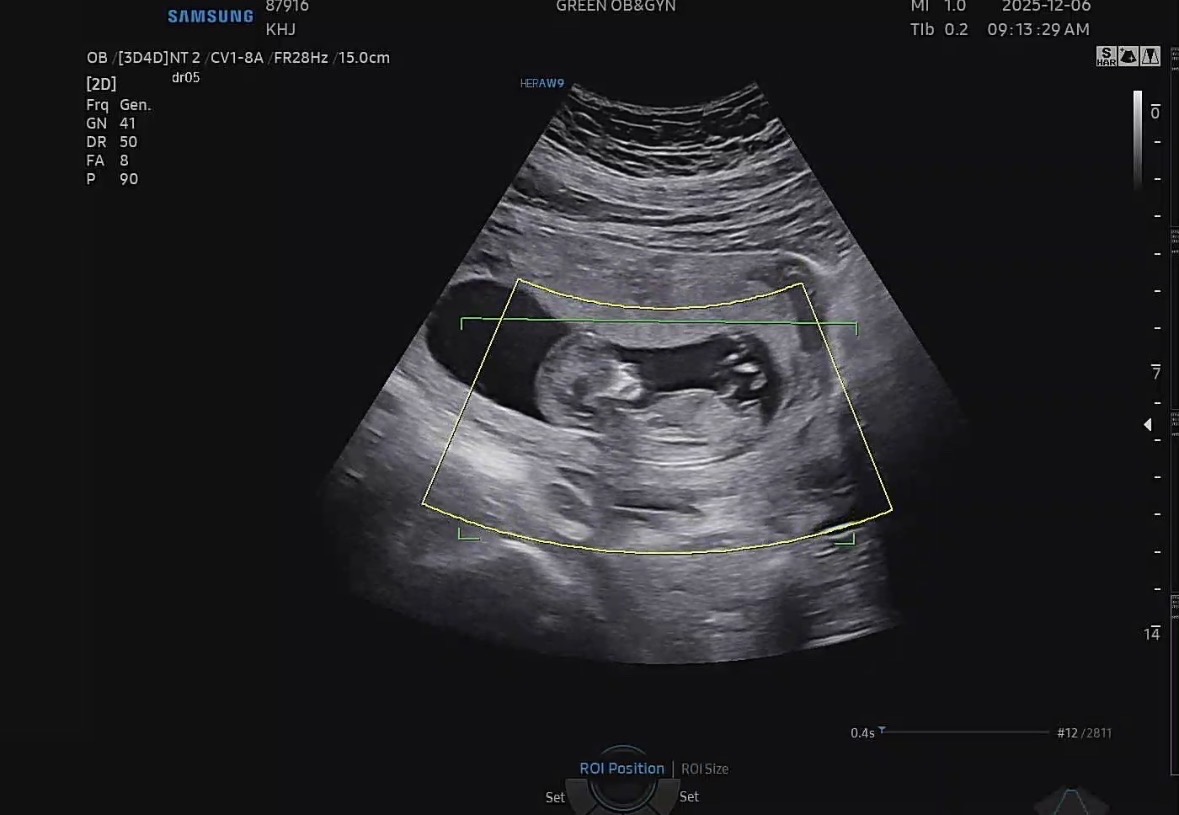

성별봐주실 분 ㅠㅠ

성별이 궁금해요오